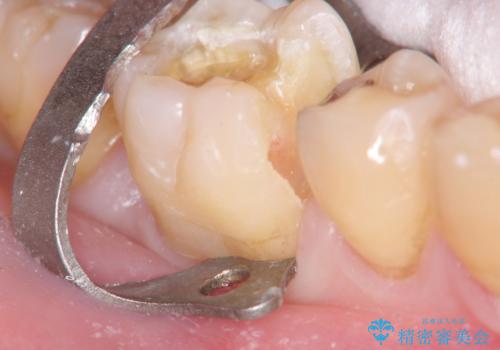

歯の神経を残す、丁寧な虫歯の除去

マイクロスコープ、拡大鏡を用いて治療を行うことで虫歯を取り切ることと必要以上に歯を削らず真剣を温存することのできる確率が高まります。

虫歯治療後の予後をより良くするために、虫歯を取り切ること精密な修復物の装着が必須となります。